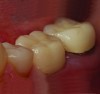

A 64-year-old woman presented with a chief complaint of food packing to the front of her implant. Clinical and radiographic examination revealed an existing Straumann Soft Tissue Level (RN) implant (Straumann, straumann.us) for tooth No. 19, restored with a prefabricated solid abutment and a PFM crown. The mesial marginal ridge of the PFM No. 19 was fractured, leaving an open proximal space between No. 19 and No. 20 (Figure 1).

Fig 1. The mesial marginal ridge of the PFM tooth No. 19 is fractured, leaving an open proximal space between teeth Nos. 19 and 20.

Figure 1